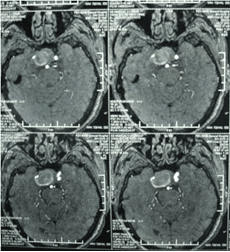

經(jīng)顱多普勒

頸內(nèi)動脈虹吸段巨大動脈瘤(約3cm ×3cm